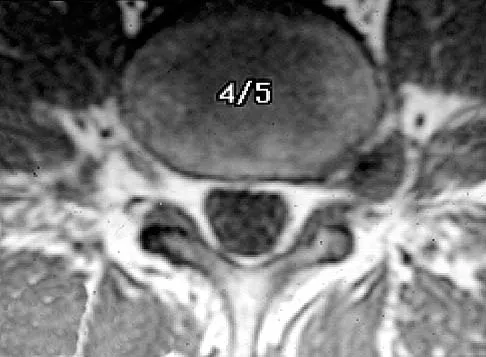

The MRI findings shown in Figure 51 would most likely create which of the following signs and symptoms?